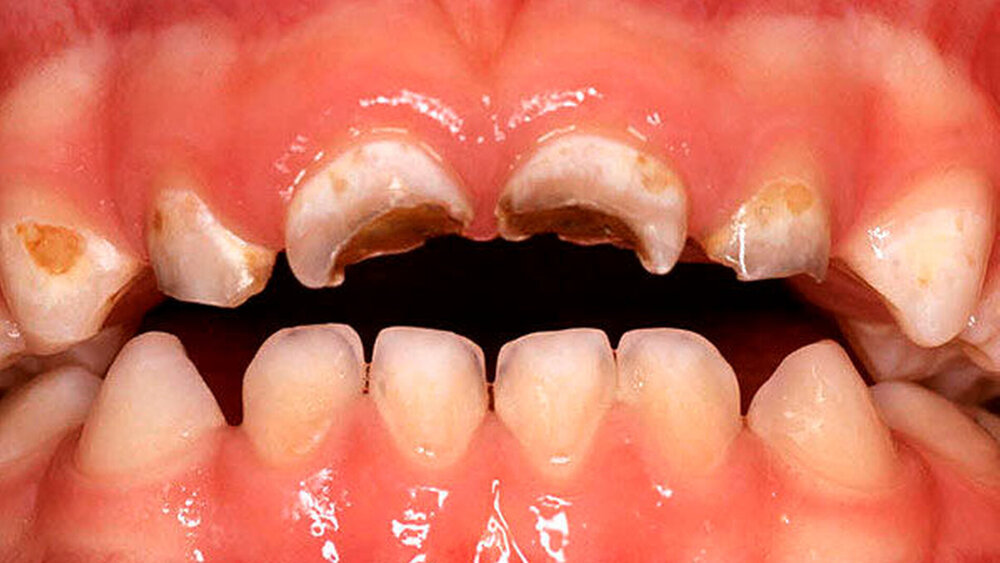

Allgemein lassen sich zwei Problemgruppen identifizieren: Die erste sind Kleinkinder mit massiver Flaschenkaries, die aufgrund des Alters und der Schwere des Befunds nur in Allgemeinanästhesie behandelt werden können. Zur zweiten Gruppe gehören ältere, behandlungswillige Kinder mit kariösen Defekten, bei denen die „einfache“ Füllungstherapie nicht mehr möglich ist, da eine pulpanahe Karies vorliegt. Trotzdem können auch Generalisten zufriedenstellende und schnelle Therapien anbieten, wenn das klinische Wissen dem aktuellen Stand der Kinderzahnheilkunde entspricht.

Zentraler Anspruch der Kinderzahnheilkunde ist: Jeder Milchzahn sollte (wenn überhaupt) nur einmal behandelt werden. Daher sind frühzeitige sowie regelmäßige zahnärztliche Kontrollen unerlässlich. Neben einer soliden klinischen Untersuchung (Karies, Zahnfarbe, Schwellung, Rötung, Fistel, Zahnbeweglichkeit in Abhängigkeit von Zahnwechsel, Zustand der Nachbarzähne) spielt die röntgenologische Diagnostik (Umfang der Karies, interradikuläre Aufhellungen, Resorptionen, Lage des Zahnkeims) für die vorausschauende Planung und für die erfolgreiche Therapie eine wichtige Rolle. Vor allem die Röntgenuntersuchung bringt meistens einen entscheidenden Mehrwert, da die Karies bei Kindern aufgrund der breiten, flächigen Approximalkontakte klinisch oft sehr schwer zu diagnostizieren ist (Abbildung 1) [Fuks, 2005].

Um den Erhalt der Oberkieferfrontzähne bei der Nuckelflaschenkaries oder nach Frontzahntrauma einzuschätzen, hat sich der Aufbiss bewährt. Falls das Kind den Mundfilm nicht toleriert, stellt das Orthopantomogramm keine Alternative zur exakten Diagnostik dar und sollte nur im Ausnahmefall, zum Beispiel bei Verdacht auf eine Durchbruchstörung, Verlagerung, allgemeines Trauma oder Molaren-Inzisivi-Hypomineralisaton Anwendung finden. Zudem kann über die Akzeptanz des Röntgens die generelle Compliance getestet werden. Scheitert eine intraorale Aufnahme, so ist auch die Compliance für eine Füllung oder gar eine Krone nicht gegeben.